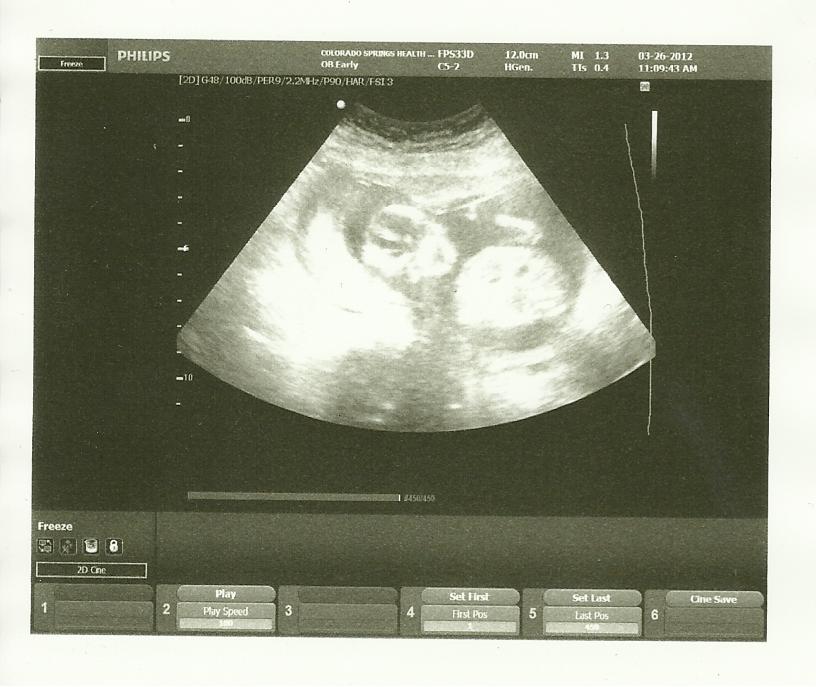

My ob did a really quick scan at my last appointment, she wouldn't do a nub shot : (

Any fun guesses on the skull theory?!?

Cant tell sorry x

Hard to tell front on but i will guess boy, just for fun though goodluck.